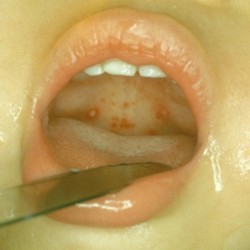

- 2-3 день – на поверхности слизистой гортани образуется сыпь, которая выглядит как мелкие пузырьки, наполненные серозной жидкостью (они ярко красного цвета, который на следующие сутки может смениться белесым, см. фото). На этом этапе температура становится ниже, чем в первый день, однако симптомы интоксикации нарастают. Появляется ломота во всем теле, ребенок жалуется на жажду, боль в горле, невозможность нормально глотать пищу и воду. На 3-й день температура вновь повышается, достигая своего пика, миндалины могут увеличиться (хотя не всегда), малыш чувствует себя тяжело, становится капризным, отказывается от еды, плохо спит;

Отличить герпесную ангину у ребенка от других ее видов достаточно просто – на поверхности горла на 2-3 сутки появляются болезненные папулы ярко-красного цвета.

Из-за оттенка родителям кажется, что они наполнены кровью, но спустя сутк, окраска пузырьков меняется. В них отчетливо просматривается серозное содержимое прозрачного или белесого цвета.

Диаметр высыпаний может достигать 1-2 мм, а их количество варьируется от 6 до 12 штук. У детей с ослабленным иммунитетом болезнь протекает волнами, на третьи сутки к уже высыпавшим пузырькам могут добавиться еще 5-6 штук, а температура при этом повышается.

Слизистый эпителий гортани у малыша выглядит отечным и покрасневшим, с явными признаками воспаления. Боль в горле может быть интенсивной настолько, что ребенку тяжело есть и пить, а легкое прикосновение к язвочкам доставляет массу дискомфорта.

Каждая папула окружена ярко-красным венчиком, а серозное содержимое из нее выдавить невозможно, и нельзя пытаться этого делать. Через 3-4 дня пузырьки вскроются самостоятельно, а корки и эрозии заживут.

На мягком нёбе наблюдаются везикулы (пузырьки)

Характерным признаком герпетической ангины являются пузырьки, заполненные прозрачной жидкостью

На слизистой оболочке мягкого нёба может отмечаться вирусная энантема (мелкоточечная сыпь ярко-красного цвета). На нёбных миндалинах и задней стенке глотки характерным признаком будет наличие везикул (пузырьков) с прозрачным содержимым внутри.

Сыпь представляет собой мелкие пузырьки, наполненные серозной жидкостью. Через некоторое время они лопаются, происходит их слияние, что приводит к образованию язвочек, покрытых плёнкой. Благодаря таким признакам диагностика заболевания становится более точной.

- Нёбные дужки, миндалины, нёбо покрываются мелкими плотными пузырьками (везикулами) диаметром 5 мм, которые через некоторое время наполняются жидкостью.

- Спустя сутки они вскрываются, а вместо них образуются серо-белые язвы, которые могут сливаться. Поражённая слизистая начинает заживать через 6–7 дней.

Диагностировать герпесную ангину позволяет свойственные ей высыпания на нёбе, миндалинах и задней стенке глотки.

Начало болезни довольно острое и сопровождается резким повышением температуры, которая сохраняется 3 дня, болью в процессе проглатывания, появлением во рту везикул, наполненных жидкостью. В дальнейшем часть из них пропадает, а остальные вскрываются. Мелкие пузырьки сливаются в целые участки, обычно их не больше 15.